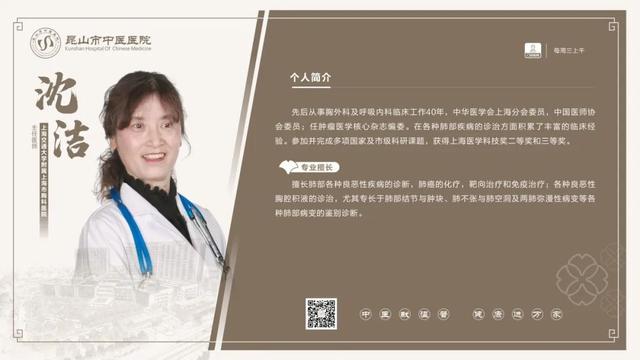

6��23��-6��29�������dz���ר�ҽ���

6��23��

6��25��